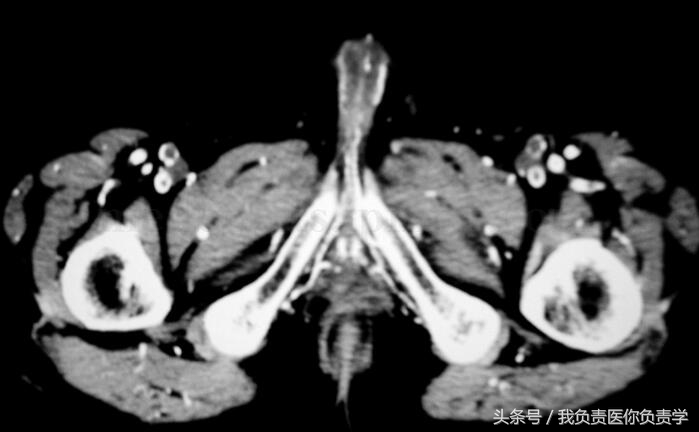

其他检查:左右足正斜位片:检查所见构成双足各骨骨质疏松,未见明确骨质增生及破坏,未见骨折,双足各关节未见异常。印象诊断双足骨质疏松。胸片(图35‐5):心、肺、膈未见异常。胸部CT:检查所见两肺透亮度减低,呈毛玻璃样改变,以双上肺明显,右下肺后基底段可见钙化点,余两肺未见结节及片状病灶,气管及叶、段支气管无狭窄,肺门、纵隔未见明确肿大淋巴结。心脏无扩大,胸膜无结节,胸腔无积液,胸壁未见确切异常。印象诊断:双肺呈毛玻璃样改变,考虑慢性肾衰竭引起心肺改变。泌尿系彩超:左肾区不纯液性包块;右下腹移植肾血流显示较稀少。下腹部CT:检查所见左侧髂窝可见移植肾,其形态、大小未见异常改变,移植肾内侧可见扩张的输尿管,前列腺形态、大小正常,内见散在钙化斑,膀胱充盈不佳,膀胱精囊角存在,直肠结构未见异常,盆壁未见肿大淋巴结,盆腔、双侧腹股沟区、双侧臀部血管广泛钙化。印象诊断:左侧髂窝移植肾形态、大小未见异常改变,左侧输尿管扩张积水;盆腔、双侧腹股沟区、双侧臀部血管广泛钙化。腹部CT(图35‐6):双肾皮质变薄,并见大量蛋壳样钙化,双肾盂、肾盏及左侧输尿管上段扩张积水;移植肾大小、位置、形态未见明显异常;腹部血管广泛钙化;胆囊结石。心电图(图35‐7):窦性心律,大致正常心电图。

图35‐6 盆腔CT 平扫:盆腔、双侧腹股沟区、双侧臀部血管广泛钙化